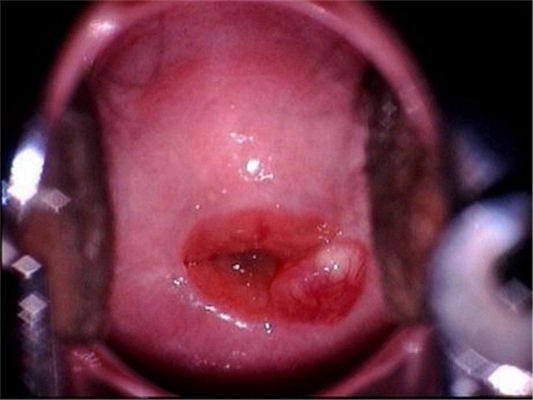

重度宮頸糜爛圖 (21)